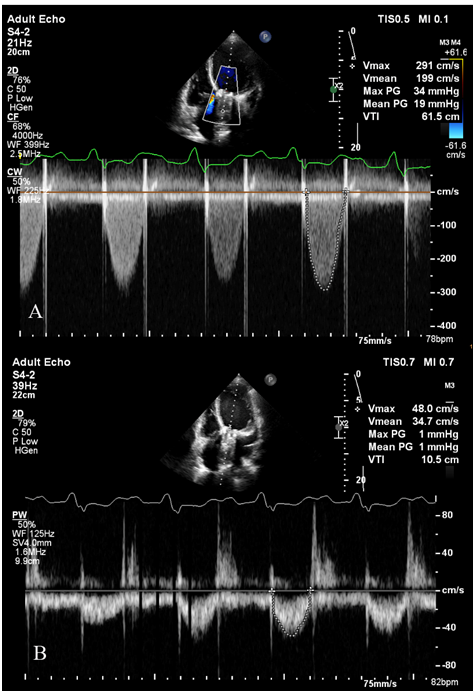

The initial transthoracic echocardiography (TTE) showed an ejection fraction of about 15%, moderate to severe right ventricular dysfunction, (TAPES, 12mm), and significant pulmonary hypertension with systolic pulmonary arterial pressure of about 55mmHg. Hemodynamic study of AV prosthesis showed mean AV gradient of 20mmHg, an acceleration time of 115milliseconds and DVI (LVOT VTI/AV VTI) of about 0.17. It also showed small moving particles on the ventricular side of the aortic valve, mostly suggestive of a clot. The patient was admitted to the cardiac care unit (CCU) and initially managed for pulmonary edema as well as heart failure using an infusion of furosemide. The patient’s symptoms improved by 2days and the patient was transmitted to the ward with the termination of her infusions, but one day after discontinuation of her infusions the patient’s dyspnea worsened and we had to transfer her to CCU and start infusions again (Figure 1).

Figure 1 The initial transthoracic echocardiography of the patient showing A. prosthetic aortic valve (AV) mean gradient and VTI; B. Left ventricular outlet (LVOT) mean gradient and VTI. The DVI (LVOT VTI/AV VTI) was: 0.17.